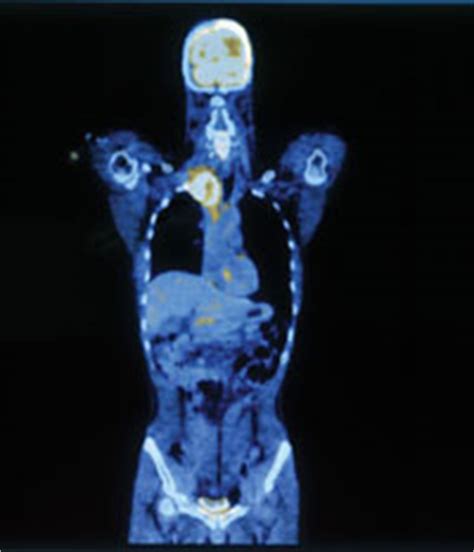

How can i tell if my dog has brain damage? Cats and dogs can have strokes, but they seem to occur less frequently in pets than in people. Cats are notorious for hiding their pain. Cat scans can be given for a variety of reasons but commonly they are given for cancer and tumor related illnesses and examinations. Who might my treatment team include, and for how long will i continue to see them?

Spotlight on Brain Tumors | NIH News in Health from newsinhealth.nih.gov Benign tumors are not aggressive and normally do not spread to surrounding tissues, although they can be serious and even life threatening. More importantly, psychological factors can influence how much emphasis we attribute to our symptoms. We immediately went to the vet and they are running a. How can i tell if my dog has brain damage? This youtube channel provides high quality pet health advice to everyone who needs it all over the world. Sometimes a cat will hide if they are unfamiliar with a space or new to your family, but paschke said if that is the case she recommends providing them with their own personal space so they can breathe. Most strokes involve blood clots, but some are caused by tumor cells, bacteria, and parasites. How do you tell if someone is a professional carpenter?